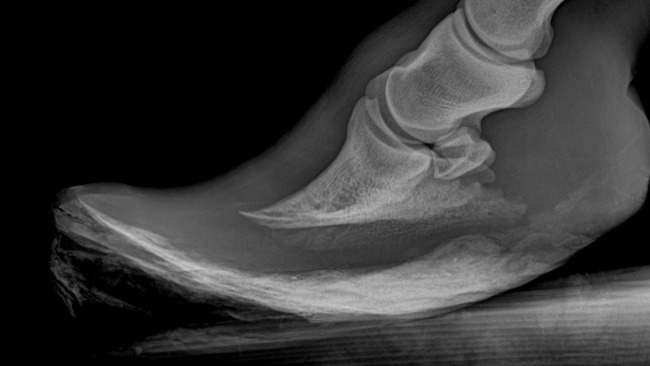

jest źle. Laluś miał wykonane zdjęcia RTG zarówno łopatki, jak i kopyt. Deformacja łopatki wymaga podawania leków, dodatkowo Laluś ma ochwat, a co za tym idzie przed nim wielomiesięczne leczenie, co wiąże się z dużymi kosztami.

Opis weterynaryjny: Obrzęk i deformacją prawej kończyny piersiowej w okolicy stawu ramiennego- badanie radiologiczne wykazało znaczne zmiany zwyrodnieniowe, deformację stawu barkowego

Nieprawidłowe kopyto krzywe lewa kończyna piersiowa znaczne zaniedbanie w werkowaniu kopyta wyrastanie puszki kopytowej stosowne do postawy rozwartej.

Zalecenia: Terapia przeciw bólowa i przeciw zapalna w celu ograniczenia bólu stawu barkowego . Werkowanie kopyt uwzględniając położenie kości kopytowej w puszce kopytowej najlepiej na sedacji

Część udało się obciąć i ulżyć mu choć trochę, ale na dalsze działanie potrzebne są zdjęcia RTG i pełna diagnostyka, bo bez tego każde kolejne struganie to ryzyko, a tu już nie ma miejsca na błędy.